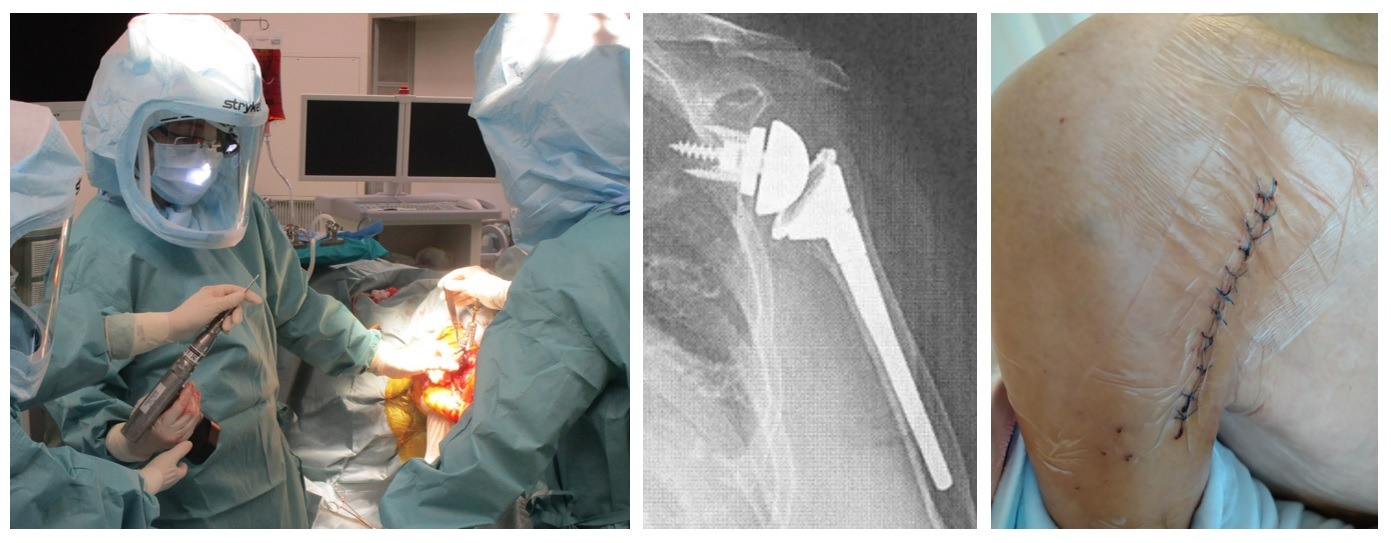

リバース人工肩関節

2014年日本国内に導入。

適応は65歳以上で腱板修復不能、挙上困難(偽性麻痺)に対して三角筋の力を利用して肩をあげる人工関節。

他に粉砕の強い骨折や高齢者の脱臼に対しても適応になることもあります。

リバース人工肩関節の手術の傷は、5~10㎝ほどです。

術後10日くらいで抜糸です。

抜糸してからシャワー許可しています。